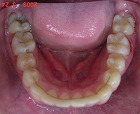

矯正後